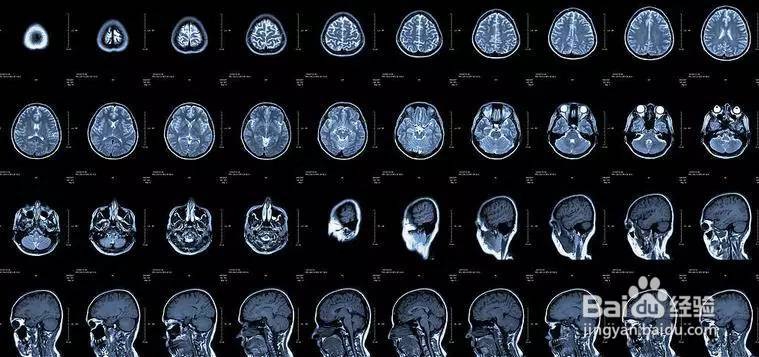

核磁共振:摇一摇再看

核磁共振机使用较强大的磁场,使人体中所有水分子磁场的磁力线方向一致,这时磁共振机的磁场突然消失,身体中水分子的磁力线方向,突然恢复到原来随意排列的状态。简单说就相当于用手摇一摇,让水分子振动起来,再平静下来,感受一下里面的振动。所以,核磁共振(MRI)也被戏说为是摇摇看的检查。